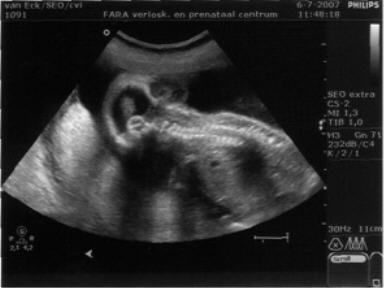

De eerste maanden verliepen zoals gewend. Mama was veel moe en groeide gestaag. Vol verwachting, maar ook wel zenuwachting, gingen we naar het echobureau voor een 20-weken-echo. Daar bleek al snel dat er iets niet goed was met ons kindje. We zagen een bult op het hoofdje, achter in de nek. De echoscopist kon ons niet verder helpen en verwees ons door naar een gyneacoloog.

Ontdaan en gespannen vertrokken we. Eenmaal thuis doken we achter internet. Wat was er aan de hand met ons kindje? We vonden medische informatie: het heette een encephalocele (ook wel geschreven als encefalocele), er worden in Nederland slechts een paar kinderen per jaar mee geboren en in de meeste gevallen is het een onderdeel van een syndroom, waardoor de kindjes niet levensvatbaar zijn. Ook lazen we verhalen van enkele ouders. In alle gevallen had hun kindje slechts kort geleefd. Wat stond ons te wachten?

De dag erna belde de gynaecoloog. De prenataal neuroloog uit Nijmegen schetste toch een heel ander beeld. Al snel konden we bij hem terecht. Op basis van de grootte en de plaats van de cele (uitstulping) gaf hij ons goede hoop: hij kende kinderen met soortgelijk beeld die gewoon op een gewone basisschool zaten. Wat een verschil met het vorige gesprek! Dit was meer dan het beste scenario tot dan toe!